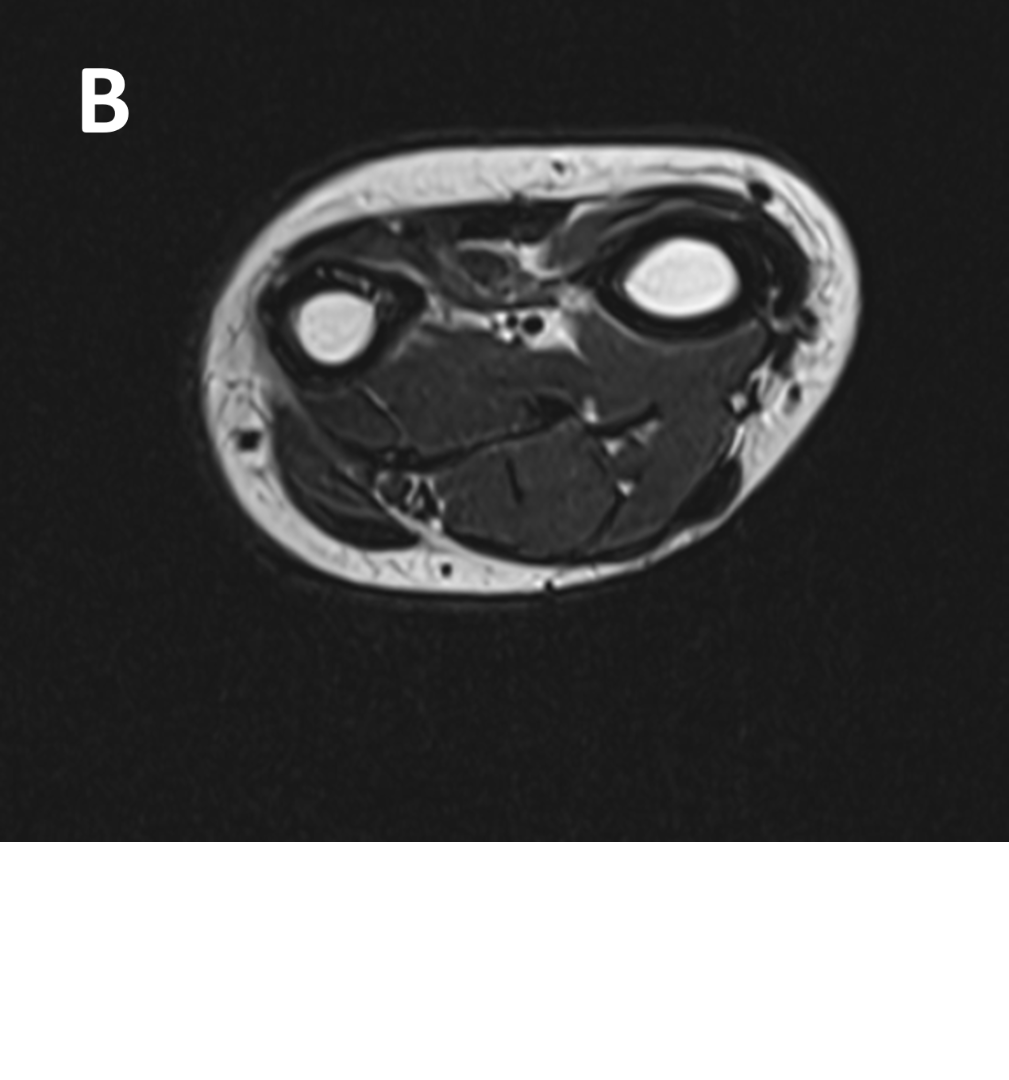

- (A,B) : MR LEFT FOREARM

- B 1 : Tract of previous intramedullary nail seen in shaft of humerus, along with mild diffuse cortical thickening.

- B 2 : Volume loss with fatty atrophy of brachioradialis, supinator, extensor carpi radialis longus and brevis muscles ,due to chronic denervation changes.